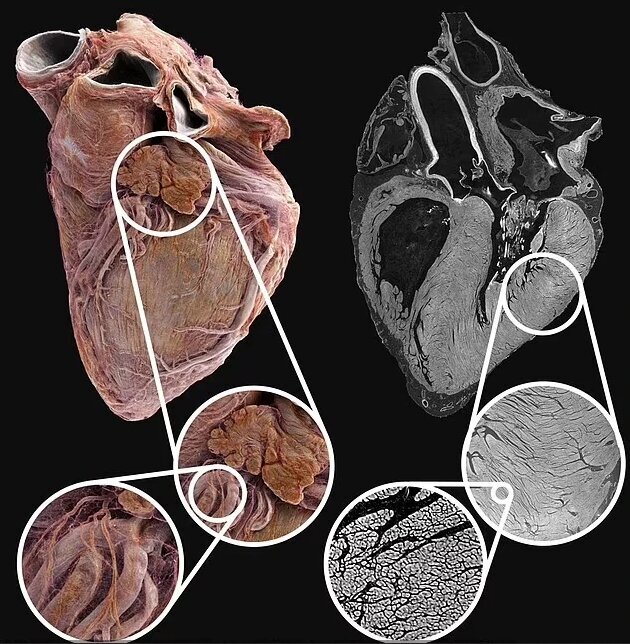

به گزارش سلام نو به نقل از روزیاتو، در این مطالعه، محققان با استفاده از تکنیک جدید اشعه ایکس موسوم به توموگرافی فاز-کنتراست سلسله مراتبی (HiP-CT)، دو قلب انسان های بزرگسال درگذشته را مورد بررسی قرار دادند: یکی متعلق به مردی ۶۳ ساله با قلبی سالم و دیگری از زنی ۸۷ ساله با سابقه بیماری ایسکمیک قلبی، فشار خون بالا و فیبریلاسیون دهلیزی.

تصاویر به دست آمده تفاوتهای قابل توجهی را بین قلب سالم و بیمار نشان میدهد. در حالی که قلب سالم شکلی مشخص و تعریف شده دارد، قلب بیمار گردتر بوده و رگها و فیبرهای عضلانی آن پژمرده به نظر میرسند.

این تکنیک جدید قادر است تصویری سه بعدی از قلب ارائه دهد که ۲۵ برابر دقیقتر از اسکنرهای CT معمولی است و حتی میتواند در برخی نقاط تا سطح سلولی بزرگنمایی کند.